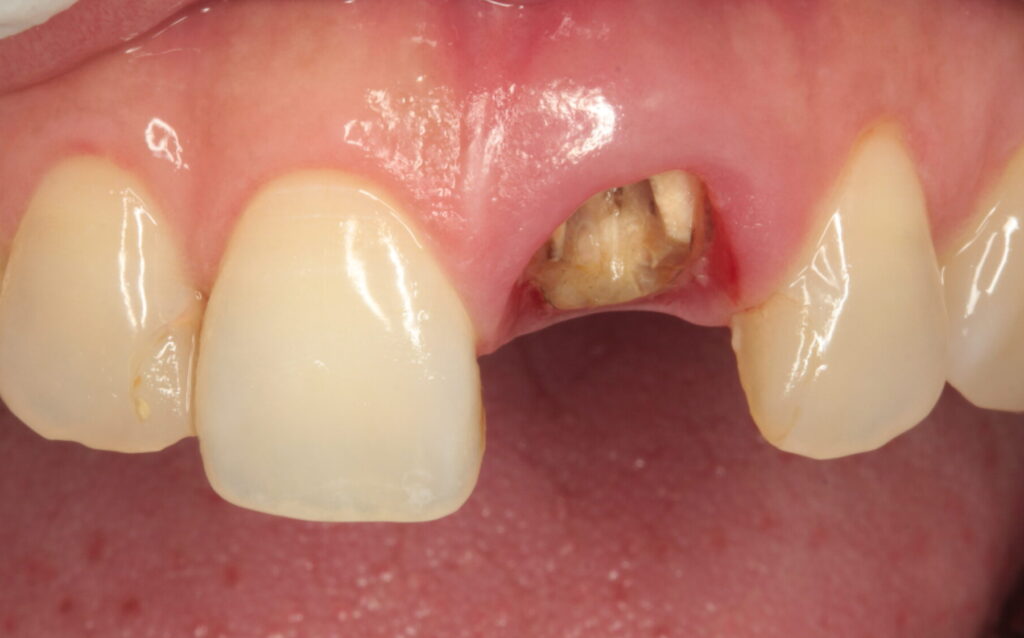

差し歯した歯の歯根水平破折症例写真

1、術前の状態 前歯をぶつけて差し歯が脱離して同時に歯根が折れてしまった。 歯根には破折線(ひび)が認められたが炎症はなく、破折線に接着材を流し保存する事とした。(図1の状態)